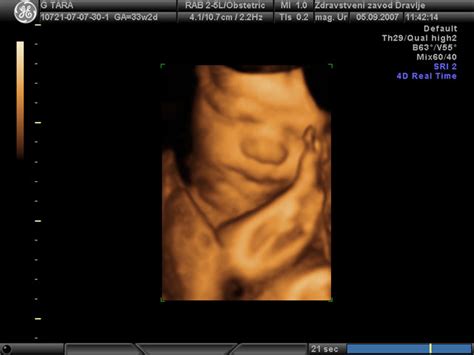

Z ultrazvokom se redno spremlja rast ploda in ocenjuje količina plodovnice. Če zdravniki odkrijejo preveč ali premalo plodovnice, preverijo, če obstaja možen vzrok. Lahko se opravijo krvne preiskave, da bi preverili, ali so prisotne okužbe ali sladkorna bolezen pri materi, ki bi lahko vplivale na količino plodovnice. Ultrazvok in drugi testi, vključno z morebitno amniocentezo, se lahko opravijo za preverjanje prirojenih okvar in genetskih nepravilnosti pri plodu. Plodov srčni utrip se redno spremlja, ko plod leži pri miru in med premikanjem, kar dodatno ocenjuje njegovo dobrobit.